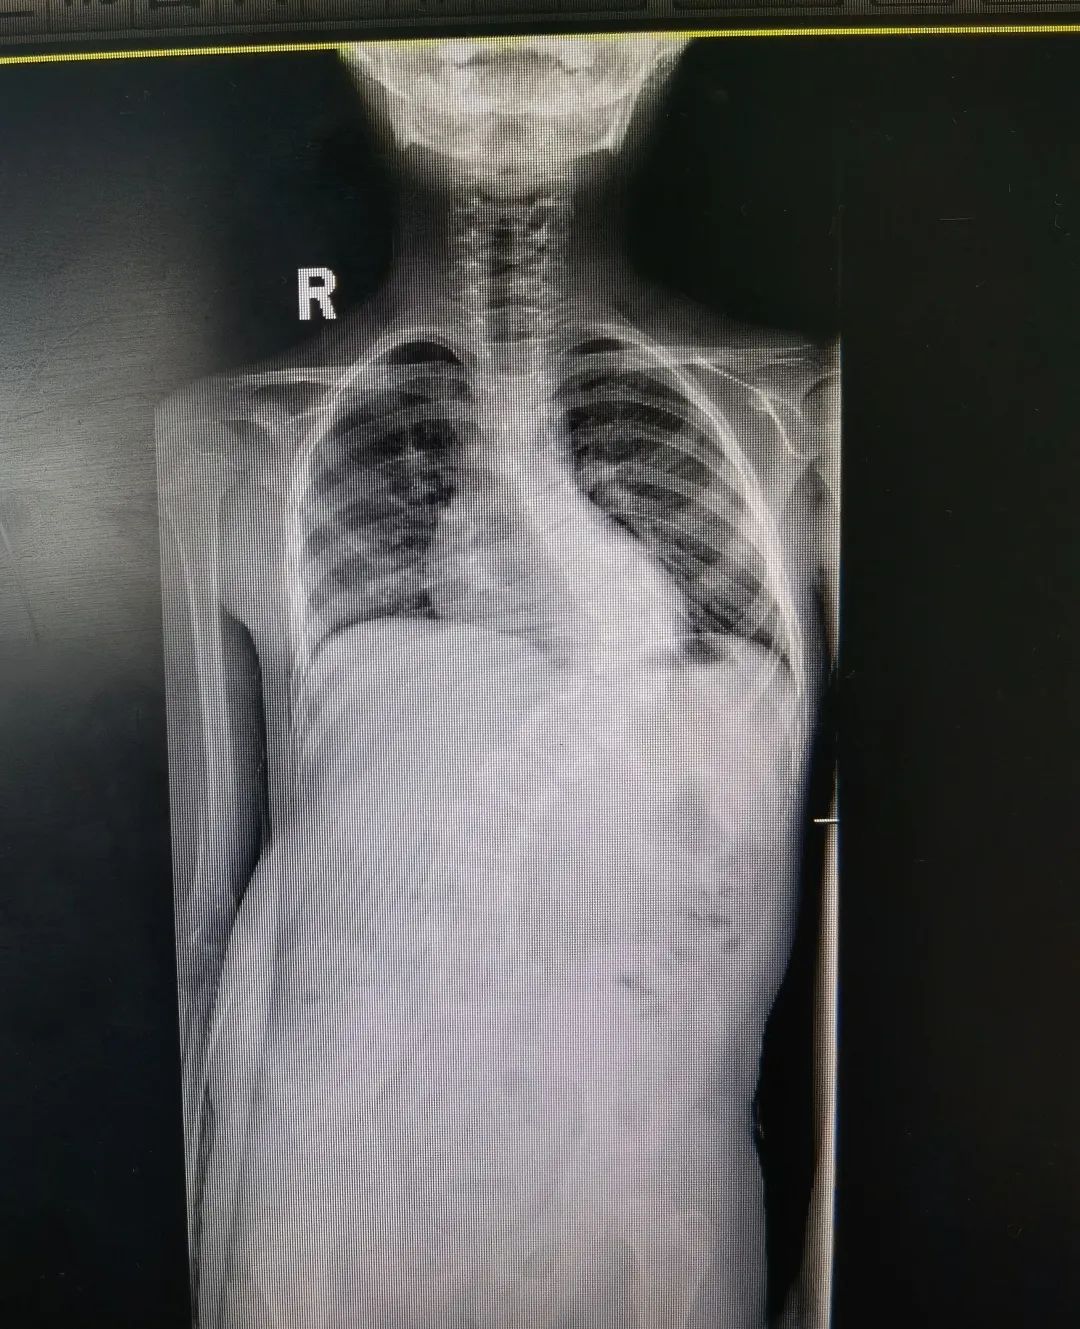

先天性脊柱侧弯半椎体畸形术前术后图

陈文昊副主任介绍,每个人的脊椎由两个成骨中心,两边合在一起,逐渐成为一个椎体。如果只有一侧成骨,则形成半个椎体。半椎体引起的脊柱侧弯和孩子平时的坐姿不良没有关系,它是由于脊柱在胚胎时期出现脊椎的分节不完全、一侧有骨桥或者一侧椎体发育不完全或者混合有上述两种因素,造成脊柱两侧生长不对称,从而引起脊柱侧弯。

“家长需要注意的是,如果孩子还没到青春期,就发现有脊柱侧弯的倾向,就要考虑是否可能是先天因素引起,建议带孩子到医院进行排查,而不是简单归为坐姿问题,不然可能会延误治疗。”陈文昊说。